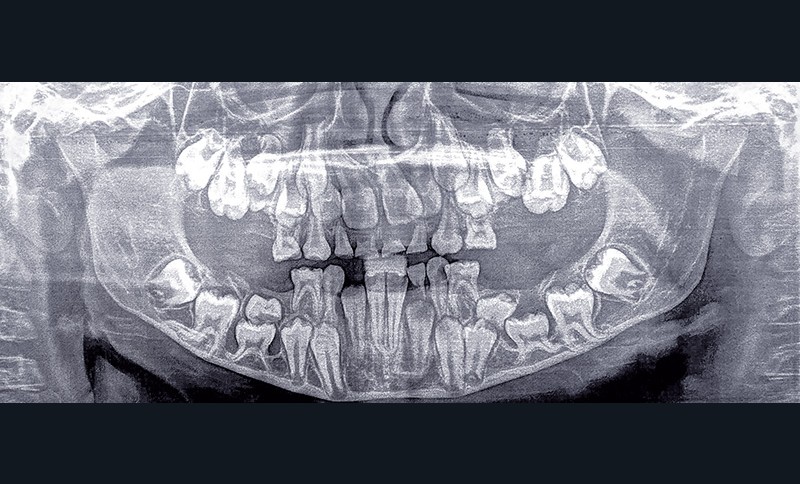

Marine consulte, avec une radiographie panoramique (fig. 1), au service d’Odontologie du CHU de Bordeaux. Elle est adressée par son chirurgien-dentiste pour un important retard d’évolution dentaire.

Radiographie panoramique

La radiographie panoramique confirme la présence de tous les germes et le retard d’évolution dentaire, mais révèle la présence des deuxièmes molaires mandibulaires temporaires incluses en position basale sous les germes des deuxièmes prémolaires permanentes. Elles présentent, comme les premières molaires mandibulaires, elles aussi incluses en position très basale, des racines très courbées au voisinage de la corticale.

Les premières molaires maxillaires sont également incluses, comme les deuxièmes molaires temporaires qui se superposent aux germes des deuxièmes prémolaires permanentes, en position apicale par rapport à ces dernières. L’interrogatoire confirme que les deuxièmes molaires temporaires maxillaires et mandibulaires n’ont jamais fait leur éruption.